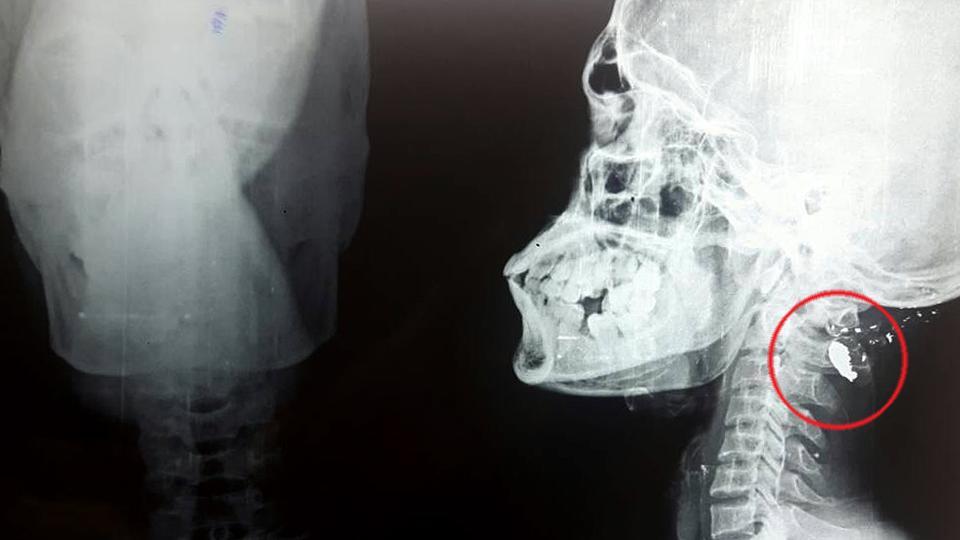

ಮೂತ್ರಶಂಕೆಗೆ ಹೋದವನ ತಲೆಗೆ ಗುಂಡು!